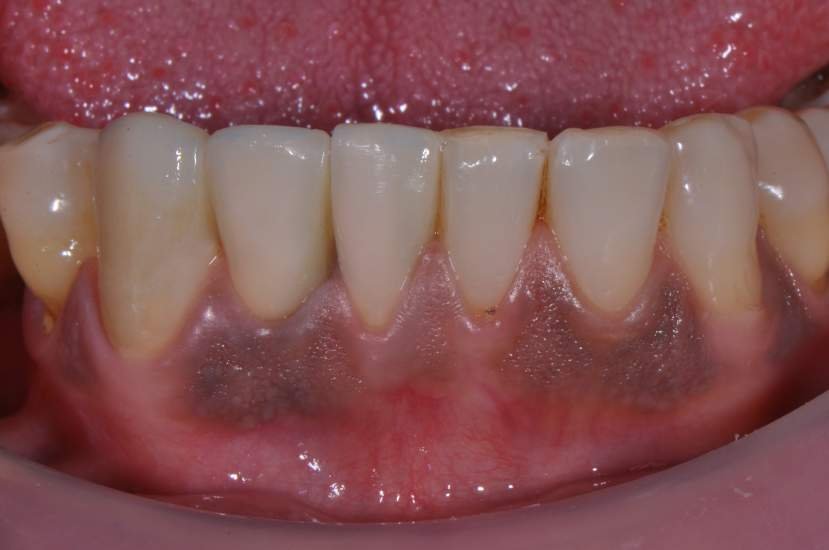

O implante de corpo único de diâmetro pequeno tem várias vantagens quando utilizado para substituir incisivos laterais superiores e incisivos inferiores. O design de uma peça, elimina o risco de afrouxamento do parafuso do pilar. Uma vez que não há micrograp entre o pilar e implante, e a quantidade de perda de óssea crestal pode também ser reduzida.6

CASO CLÍNICO

Paciente com perda do incisivo central inferior do lado direito, utilizando uma prótese fixa em zircônia com estética e adaptação deficientes.